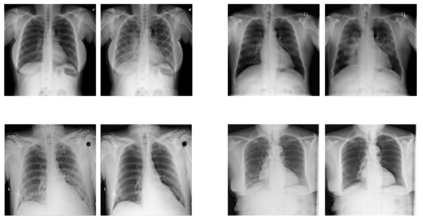

With the ongoing rise of machine learning, the need for methods for explaining decisions made by artificial intelligence systems is becoming a more and more important topic. Especially for image classification tasks, many state-of-the-art tools to explain such classifiers rely on visual highlighting of important areas of the input data. Contrary, counterfactual explanation systems try to enable a counterfactual reasoning by modifying the input image in a way such that the classifier would have made a different prediction. By doing so, the users of counterfactual explanation systems are equipped with a completely different kind of explanatory information. However, methods for generating realistic counterfactual explanations for image classifiers are still rare. Especially in medical contexts, where relevant information often consists of textural and structural information, high-quality counterfactual images have the potential to give meaningful insights into decision processes. In this work, we present GANterfactual, an approach to generate such counterfactual image explanations based on adversarial image-to-image translation techniques. Additionally, we conduct a user study to evaluate our approach in an exemplary medical use case. Our results show that, in the chosen medical use-case, counterfactual explanations lead to significantly better results regarding mental models, explanation satisfaction, trust, emotions, and self-efficacy than two state-of-the-art systems that work with saliency maps, namely LIME and LRP.